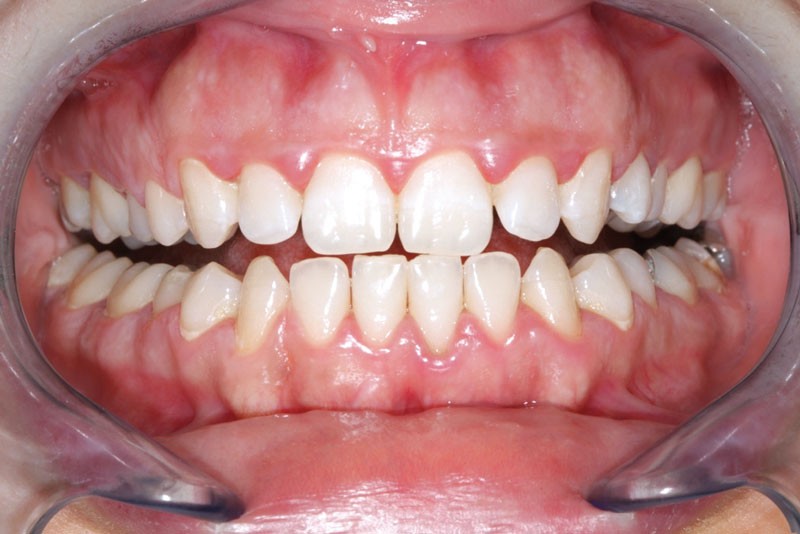

Ainsi, lors des périodes de désordres hormonaux, comme la puberté, la grossesse et la ménopause, on observe fréquemment des inflammations exacerbées qui peuvent révéler une susceptibilité de l’hôte aux maladies parodontales. (fig. 2 et 3).

Souvent, les signes cliniques régressent spontanément lorsque…